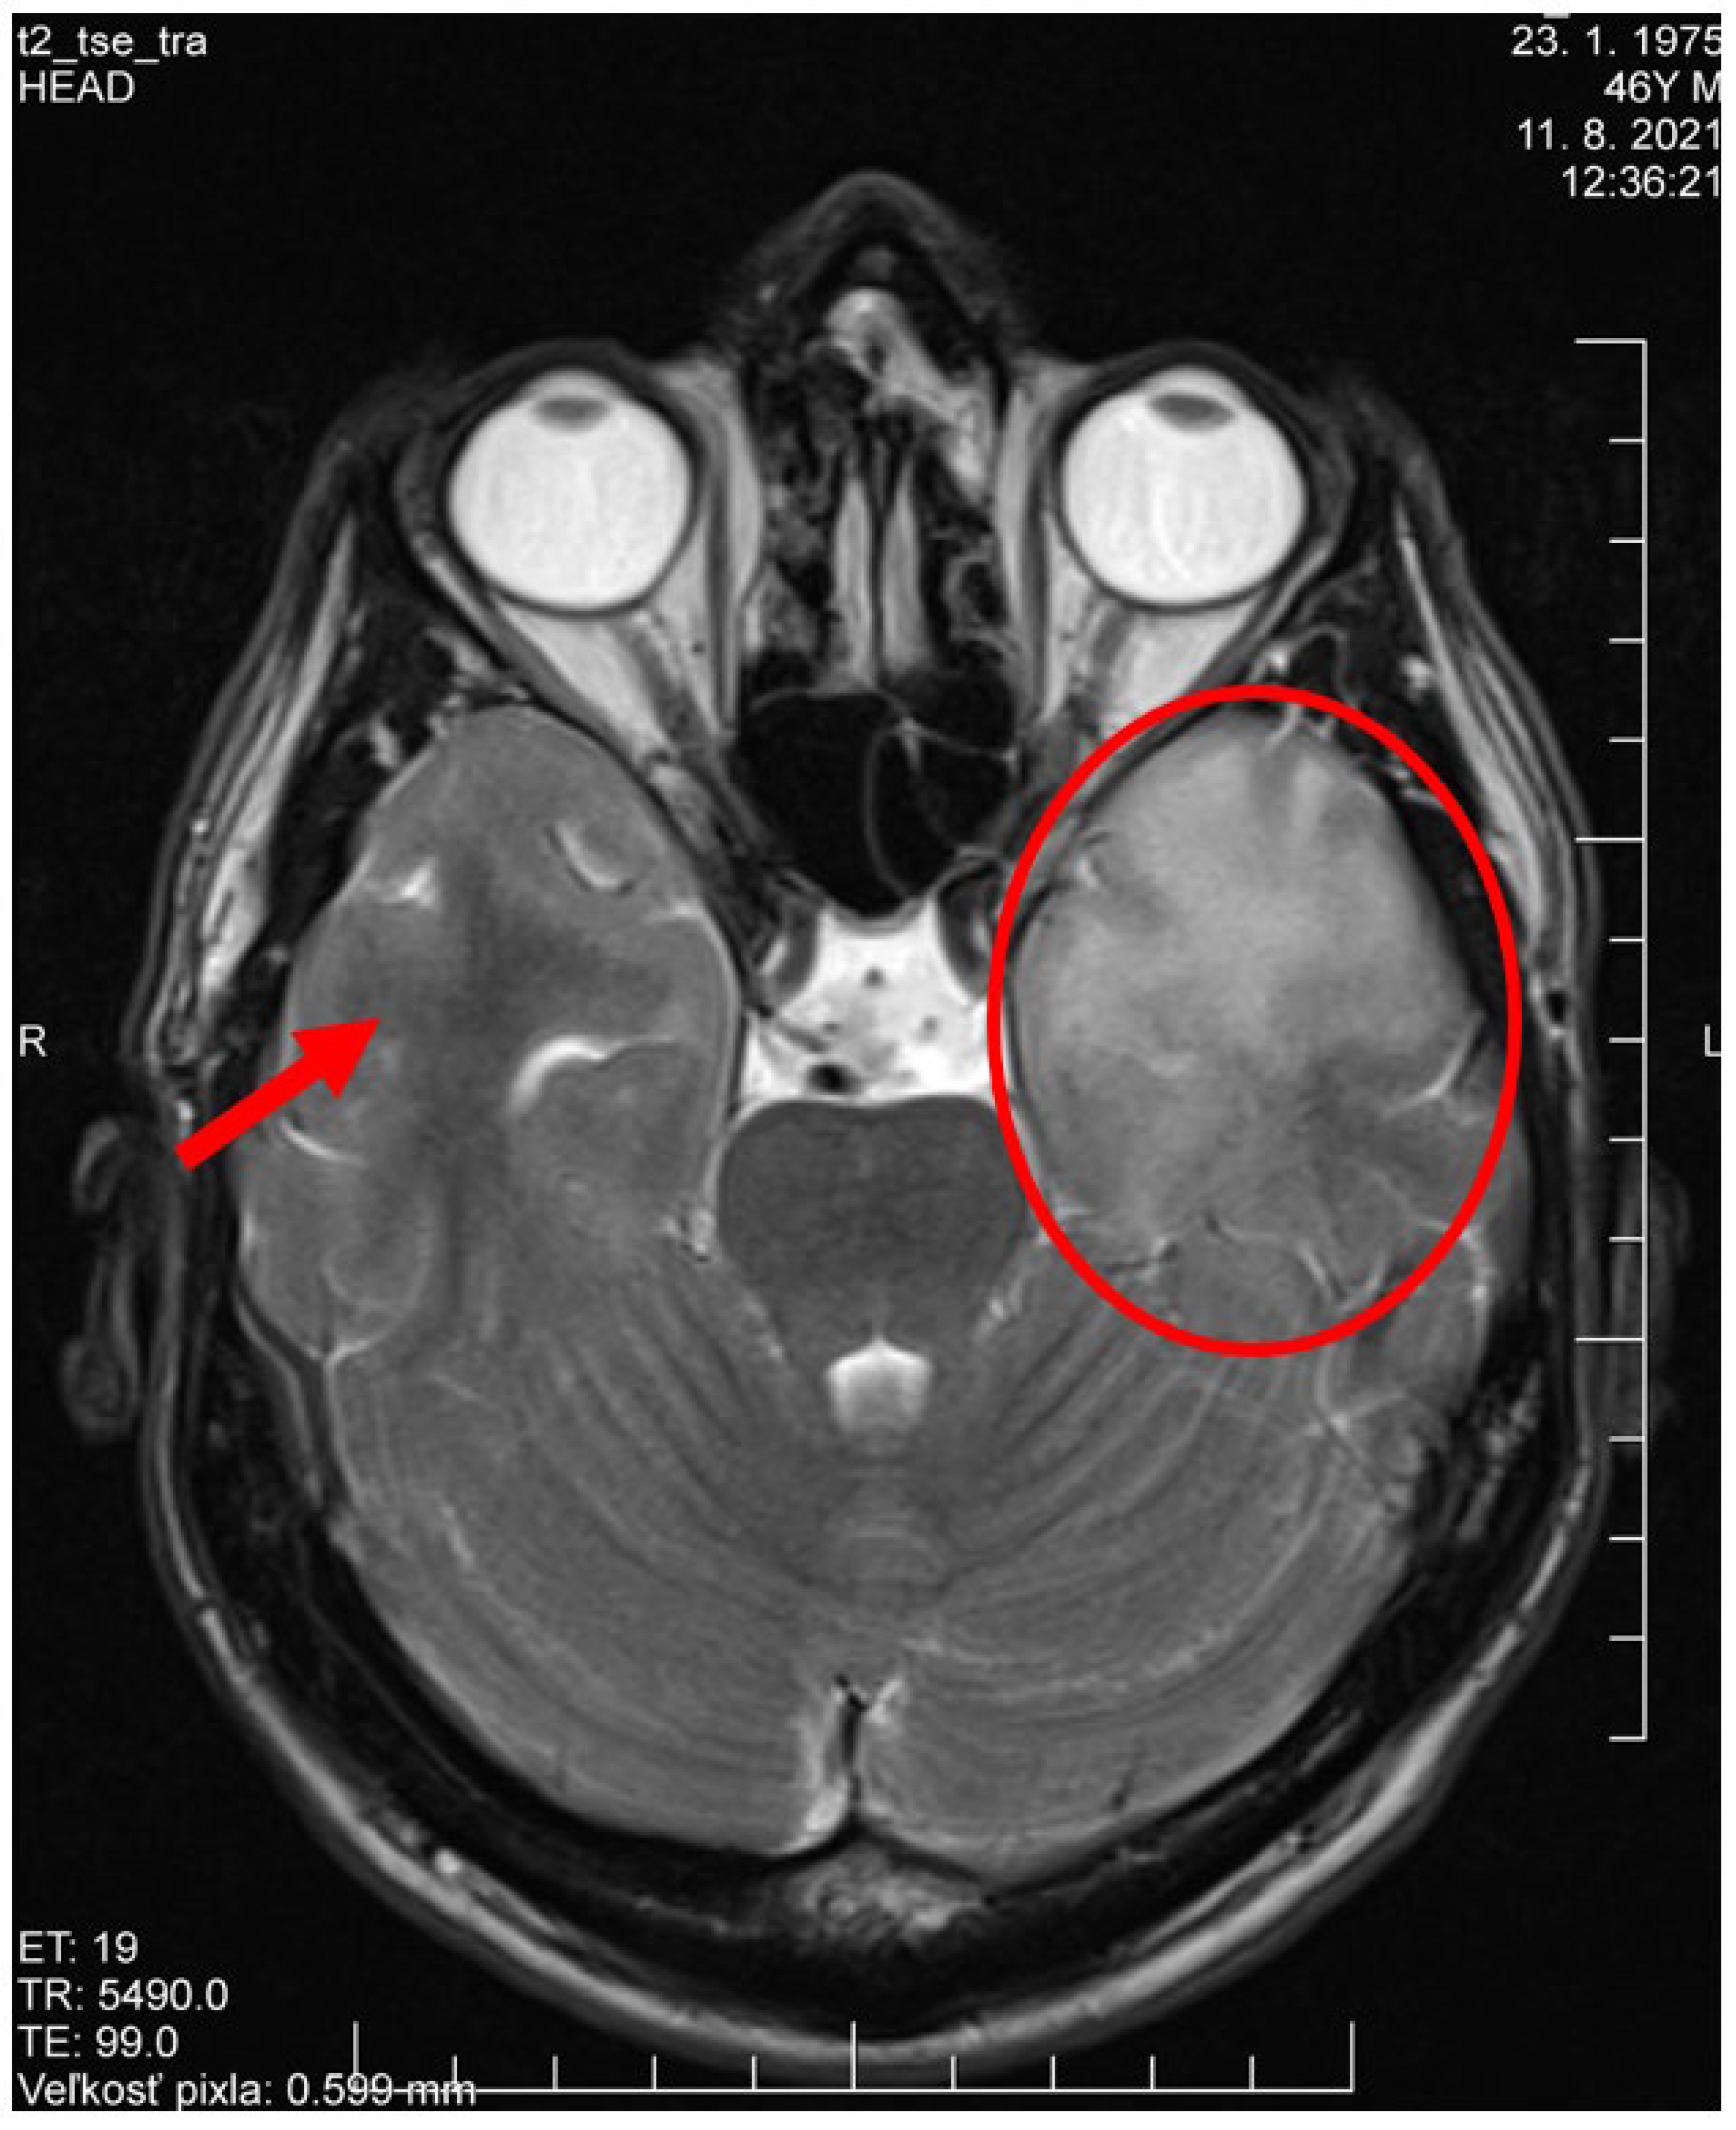

2. Case Presentation